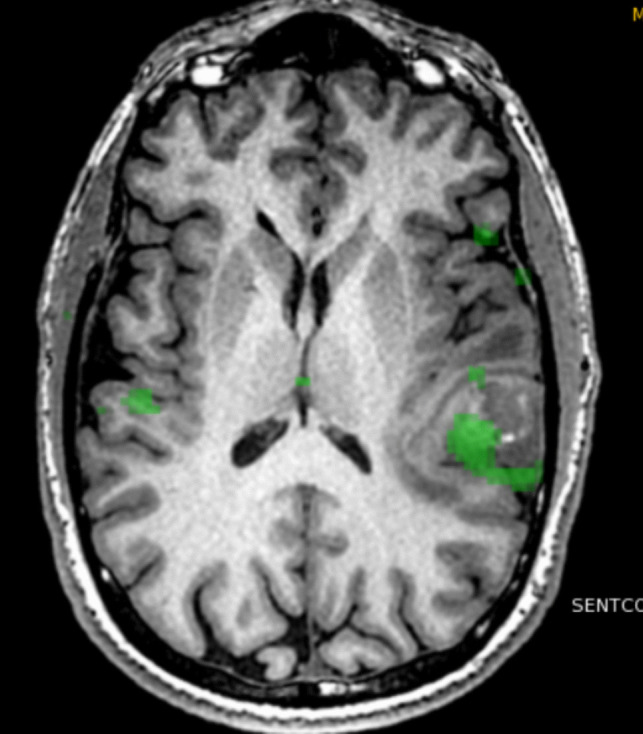

Abstract Image